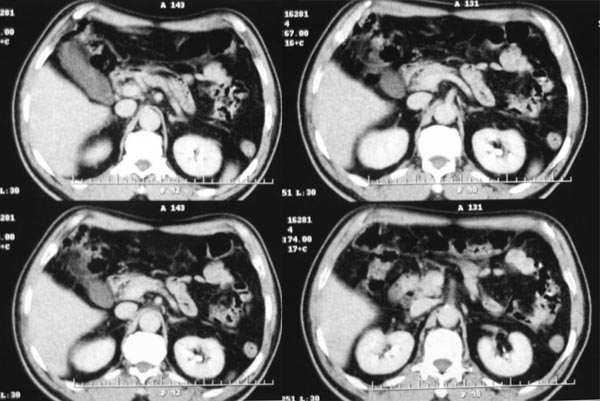

门脉期

2.病灶特点:平扫呈低密度,密度不均,中央呈更低密度;动脉期病灶周围强化较明显,高于正常肝组织,低于同层主动脉密度,中央坏死区未见明显强化;门静脉期,病灶呈低密度,低于正常肝组织密度。

肿瘤实质的强化特点符合肝癌表现,需要注意的地方还有患者可能存在门脉右支和下腔静脉内癌栓形成,这更加支持肝癌的诊断。

3、门脉期:病灶呈低密度,低于肝实质,下腔静脉见充盈缺损,说明癌栓形成

综上所述,符合肝癌伴下腔静脉癌栓形成

早期强化不是很明显,血供不是很丰富,与肝实质相比还是呈快进快出的特点,中心裂隙样坏死,支持原发性肝癌。